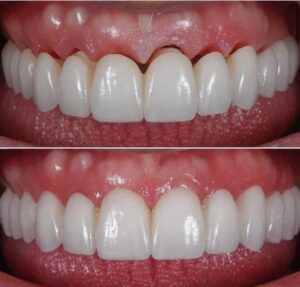

جماليات زراعة الأسنان

يتم تخطيط وتنفيذ إجراء زراعة الأسنان بعناية لضمان أن ترميم الأسنان يبدو طبيعيًا في الشكل واللون والمكان. نعطي الأولوية لراحة مرضانا بالإضافة إلى الجماليات. وهذا يتطلب مزيجًا مثاليًا من العبقرية الفنية والجراحية. لذلك ، يتم تنفيذ جميع حالات الزرع لدينا من قبل فريق من أطباء الأسنان التجميليين وأخصائي زراعة الأسنان.